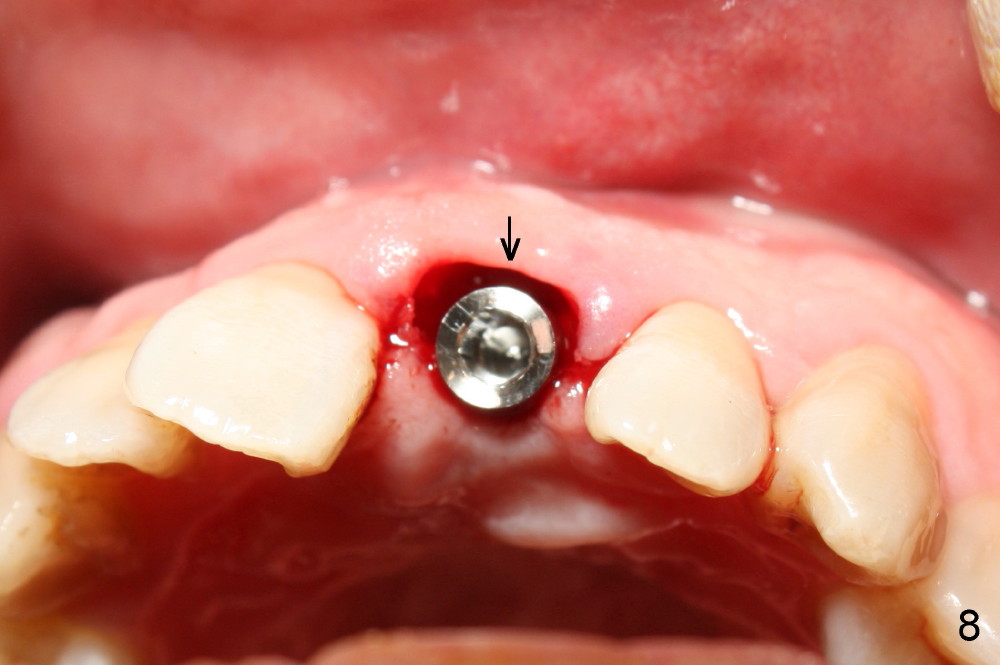

The upper right central incisor (Fig.1: #9) fractures subgingivally due to trauma for a 40-year-old man. The incisive canal is large (I) and close to the root of the central incisor. After extraction, the osteotomy (Fig.3b, 4: O) is made with 2 mm pilot drill (Fig.2: D) on the lingual wall (Fig.3a: L) of the socket (Fig.3a: S). To push the incisive canal mesially, the osteotomy is enlarged by 3.5x21 mm and 4x21 mm tapered osteotomes (Fig.5,6: O). Due to the lingual slope (Fig.7a arrow), the osteotome (blue outline) starts to deviate bucally. To reduce this tendency, the coronal portion of the lingual slope is removed (Fig.7b: yellow circle). The final implant (4.5x20 mm) is able to be placed as lingually as possible (Fig.7c, 8).

Bone expansion allows the implant (Fig.9 I) to have primary stability (insertion torque between 50 and 60 Ncm), since the cortex of the incisive canal is apparently intact. Allograft is placed in the labial gap (Fig.10, 11 *) following installation of the abutment (A). Finally an immediate provisional (Fig.10,12 P) is cemented. Fig.13,14 are taken 8 days postop. The patient returns 3 months postop (Fig.15,16). Osteointegration appears to have occurred (Fig.15 arrowheads) and is more obvious 9 months postop (Fig.17).